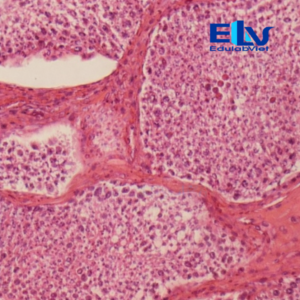

Tiêu bản tinh hoàn thỏ cắt ngang là mẫu tiêu bản hiển vi cố định thể hiện rõ cấu trúc vi thể của tinh hoàn, đặc biệt là các ống sinh tinh và các giai đoạn phát triển của tế bào sinh tinh. Sản phẩm phù hợp cho giảng dạy và thực hành môn Sinh học, Giải phẫu học, Mô học động vật.

Cấu trúc mô rõ ràng:

Quan sát rõ các ống sinh tinh, tế bào sinh tinh ở nhiều giai đoạn phát triển và mô kẽ tinh hoàn. -

Màu nhuộm đẹp – độ tương phản cao:

Tế bào được nhuộm đậm, sắc nét, giúp dễ dàng quan sát dưới kính hiển vi quang học. -